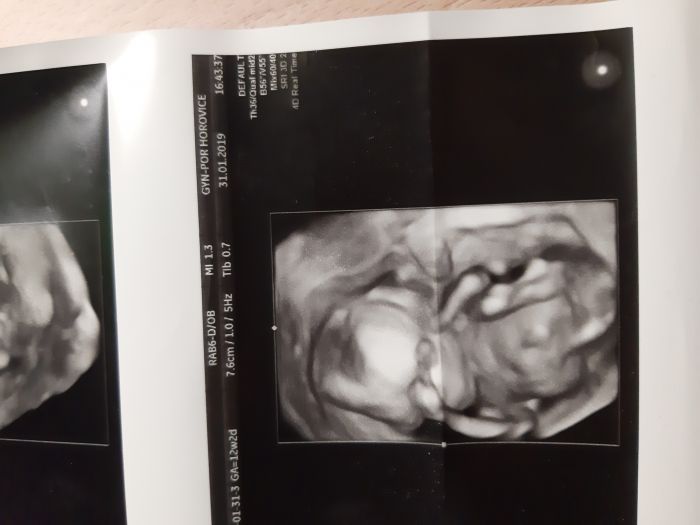

Ahojky maminky. Zajima me vas nazor. Co vidite na foto? Holcicku nebo chlapecka? Foto je cca z 22 tt. :)